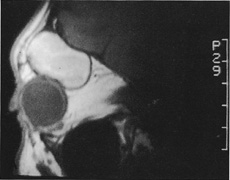

Magnetic resonance imaging is useful in selected cases, especially when evaluating the orbital cranial junction. Significant bony artifact and a lack of orbital fat in the orbital apex make CT scan resolution of the orbital apex structures poor. Because cortical bone has low signal on MRI, there is no bone artifact when viewing the orbital apex on MRI. The lack of intervening fat in the apex to provide contrast is overcome on MRI because contrast is provided by the individual nuclear characteristics of each tissue so that the orbital apex structures are visualized well. Consequently, conditions that affect the optic nerve and chiasm, such as optic nerve meningioma and glioma, generally are evaluated with MRI rather than CT scan (Fig. 2).

Fig. 2. A. Axial orbital CT scan of right optic nerve meningioma. Note lack of detail in orbital apex. B. Axial orbital MR image, same patient. Note increased detail in orbital apex owing to lack of bone artifact. C. MRI with gadolinium contrast. Note extension into brain not easily appreciated with CT scanning or MRI without contrast.

Use of a contrast agent such as gadolinium can further enhance the T1 signal intensity of lesions and is particularly helpful in imaging areas where there has been a breakdown in the blood–brain barrier. Because orbital fat produces a bright signal on T1-weighted images, orbital MR usually is performed with “fat suppression” to prevent masking of lesions. However, incomplete fat suppression can produce artifacts that may be misinterpreted as abnormal enhancement.